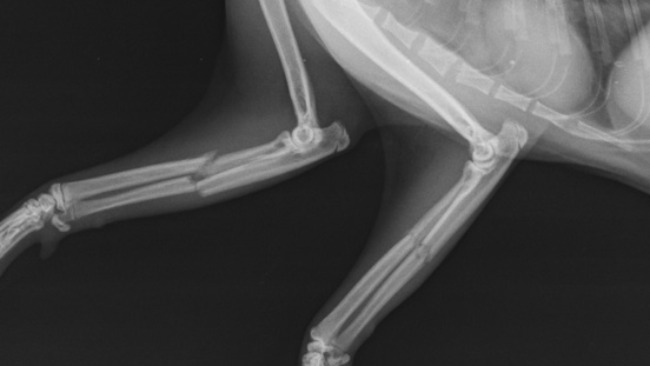

Cześć, z tej strony Janek i Irina, zbieramy pieniądze na operację naszego kota który przestraszył się nagłego ryku silnika gwałtownie przejeżdżającego auta i wypadł z balkonu na 4 piętrze. Wcześniej już reagował na podobne sytuacje nagłą ucieczką.W konsekwencji złamał sobie dwie przednie łapki (wszystkie 4 kostki). W tym stanie nie jest możliwa jego samodzielna egzystencja. Niestety operacja jest kosztowna i nie jesteśmy w stanie pomóc mu sami. Będziemy wdzięczni za każdą nawet najmniejszą pomoc.